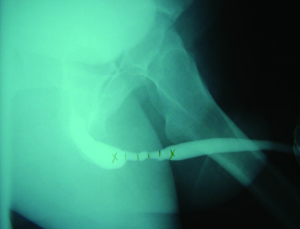

There are three key features of a stricture that a RUG must identify, including location of the stricture, the length of the stricture, and coexistent urethral pathology. In order to allow for accurate interpretation, a detailed understanding of normal urethral anatomy is critical. The urethra is typically divided into an anterior and posterior portion. The anterior urethra is comprised of the fossa navicularis, penile urethra, and bulbar urethra. The posterior urethra is composed of the membranous urethra, and prostatic urethra. The distribution of normal urethral anatomy on RUG is highlighted in Figure 2.